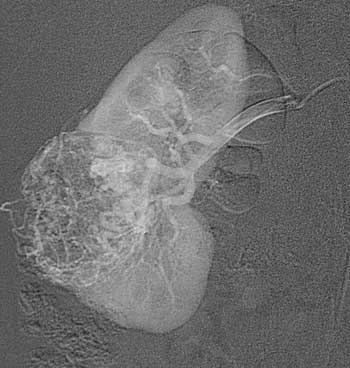

Рис. 2. Рак правой почки. Т1 N0 M0. Гиперваскулярная опухоль округлой формы с чётким контуром в форме «пылающего» шара. Выступает за пределы контура почки менее чем на 1 см.